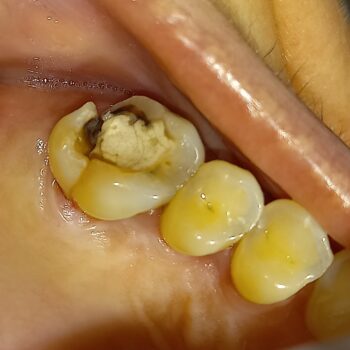

Κάταγμα απονευρωμένου δοντιού

Η ασθενής είχε ένα δόντι στο οποίο είχε ξεκινήσει η διαδικασία απονεύρωσης, αλλά καθυστέρησε να ολοκληρωθεί εγκαίρως. Τα ενδοδοντικά θεραπευμένα δόντια είναι ευαίσθητα και σπάζουν πολύ πιο εύκολα συγκριτικά με ένα ζωντανό, μη απονευρωμένο δόντι. Για το λόγο αυτό είναι σημαντικό η απονεύρωση ενός δοντιού να τελειώνει σε 2 – 3 ραντεβού σε διάστημα 2 εβδομάδων, εφόσον όλα βαίνουν καλώς και το δόντι δεν παρουσιάζει κάποιο ιδιαίτερο πρόβλημα.